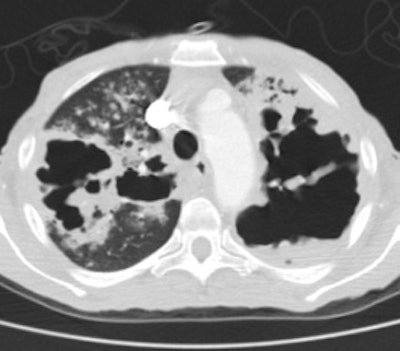

Extensive tuberculosis:

The patient below presented for evaluation of an abnormal CXR. The CT revealed bilateral extensive cavitary consolidations (essentially replacing the left lung), a large cavitary lesion in the right apex, and multiple scattered nodules and "tree-in-bud" opacities. The patient was found to have active TB.